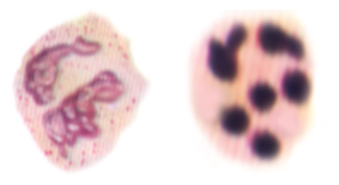

2.中性粒细胞核象右移

核右移--外周血中中性分叶核粒细胞增多,同时分5叶核以上的细胞>3%时(正常时多为3叶核)。

这是造血功能衰退或造血物质缺乏的表现,核象右移常伴白细胞总数的减少。主要见于营养性巨幼细胞性贫血,恶性贫血和用抗代谢药物,炎症恢复期可出现一过性右移。在疾病进行期,突然出现右移,提示预后不良。